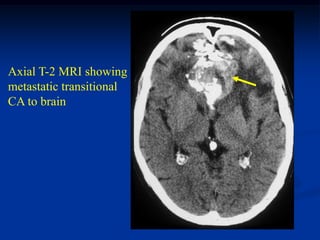

Cae #1159               Transitional Bladder CA to Bone

66 year male with metastatic

transitional bladder CA

to femur with path fracture

Axial T-2 MRI showing

metastatic transitional

CA to brain